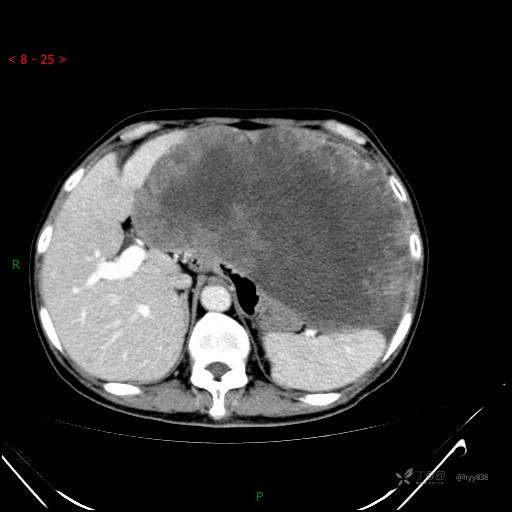

腹部CT平扫